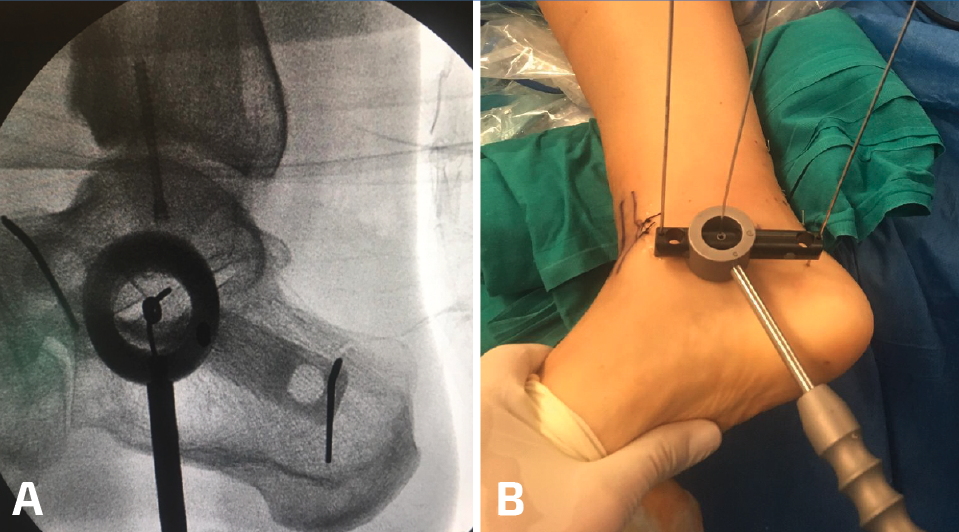

Figura 2. A y B: radioscopia e imagen clínica del uso de la guía radiotransparente para fijación articulada con pines en talus y calcáneo.

Utilizamos el fijador articulado monolateral (de tipo X-Caliber®, Orthofix). En un primer paso procedemos a colocar los pines en astrágalo y calcáneo mediante la guía radiotransparente (Figura 2), para posteriormente colocar los pines tibiales en la superficie anteromedial de la misma (a ser posible 3). Al acabar el procedimiento procedemos a realizar progresivamente una distracción de entre 7 y 8 mm (se dispone de un calibrador en el fijador que nos permite visualizar la distracción que estamos realizando) (Figura 3) bajo control radioscópico, dejando finalmente la pieza articulada totalmente libre para la movilidad tibioastragalina desde el principio. Aplicamos un vendaje compresivo de la extremidad y retiramos la isquemia (Figuras 4 y 5).